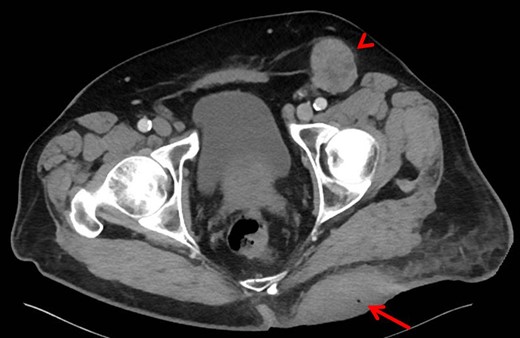

A 68-year-old Caucasian male presented to the emergency department (ED) with a painless, draining left buttock lesion. He reported that the wound had originated as a pimple a few months earlier, but had been growing over the last three weeks with foul-smelling discharge. There was no history of trauma to the area. His past medical history included a deep vein thrombosis/pulmonary embolism 20 years prior for which he was on warfarin, hyperlipidemia and tonsillectomy. On physical exam, the patient’s vitals were significant for blood pressure elevated to 153/87. On the left gluteus, a 10 × 10 cm2 non-tender lesion was noted with malodorous discharge. Labs were only significant for a therapeutic international normalized ratio of 3.07. A computed tomography (CT) of the pelvis was read as having a 9 × 10.8 × 4.2 cm3 left gluteal abscess and bulky left inguinal lymphadenopathy (Fig. 1). The patient was admitted, started on intravenous antibiotics and taken to the operating room (OR) for unroofing, debridement and incisional biopsy (Fig. 2). Pathology revealed ulcerated, necrotic skin fragments with MCC and cultures grew Enterobacter cloacae, Haemophilus parainfluenzae, Peptostreptococcus anaerobius, Peptostreptococcus asaccharolyticus. Antibiotics were de-escalated and the patient was discharged with sodium hypochlorite wound dressing changes. A chest CT was performed and showed no evidence of distant metastasis. One month later, the patient then underwent complete operative excision of the lesion down to the gluteus fascia with 2 cm margins and left groin lymph node dissection with lymphadenectomy. The resulting 13 × 15 cm2 defect was closed with a combination of fasciocutaneous advancement flaps and split-thickness skin grafting (Fig. 3). Pathological analysis showed a completely excised 11.6 cm ulcerated MCC lesion with negative margins and positive lymphovascular invasion (2/2 positive lymph nodes)—stage pT3 pN1b (Fig. 4).

Computed tomography of pelvis. The left gluteal lesion with a foci of air (arrow) signifying possible infected versus necrotic material. Left inguinal lymphadenopathy also demonstrated (arrowhead).